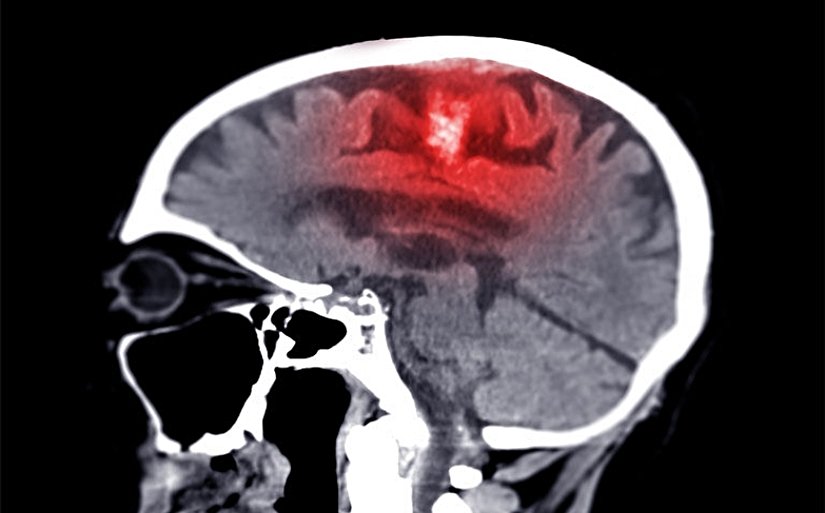

3 .İskemik Demans (Vasküler Demans)

- Beyne giden kan akışının azalması sonucu oluşur.

- En sık sebep inme veya küçük damar hastalıklarıdır.

- Belirti: Ani gelişen unutkanlık, planlama güçlüğü, dengesizlik

4. Hemorajik Demans

- Beyin kanaması sonucu gelişir.

- Sebep: Travma, hipertansiyon, anevrizma patlaması.

- Belirti: Ani bilinç değişikliği, hafıza ve konuşma bozuklukları.

- Beyin dokusu kanla zarar görür.